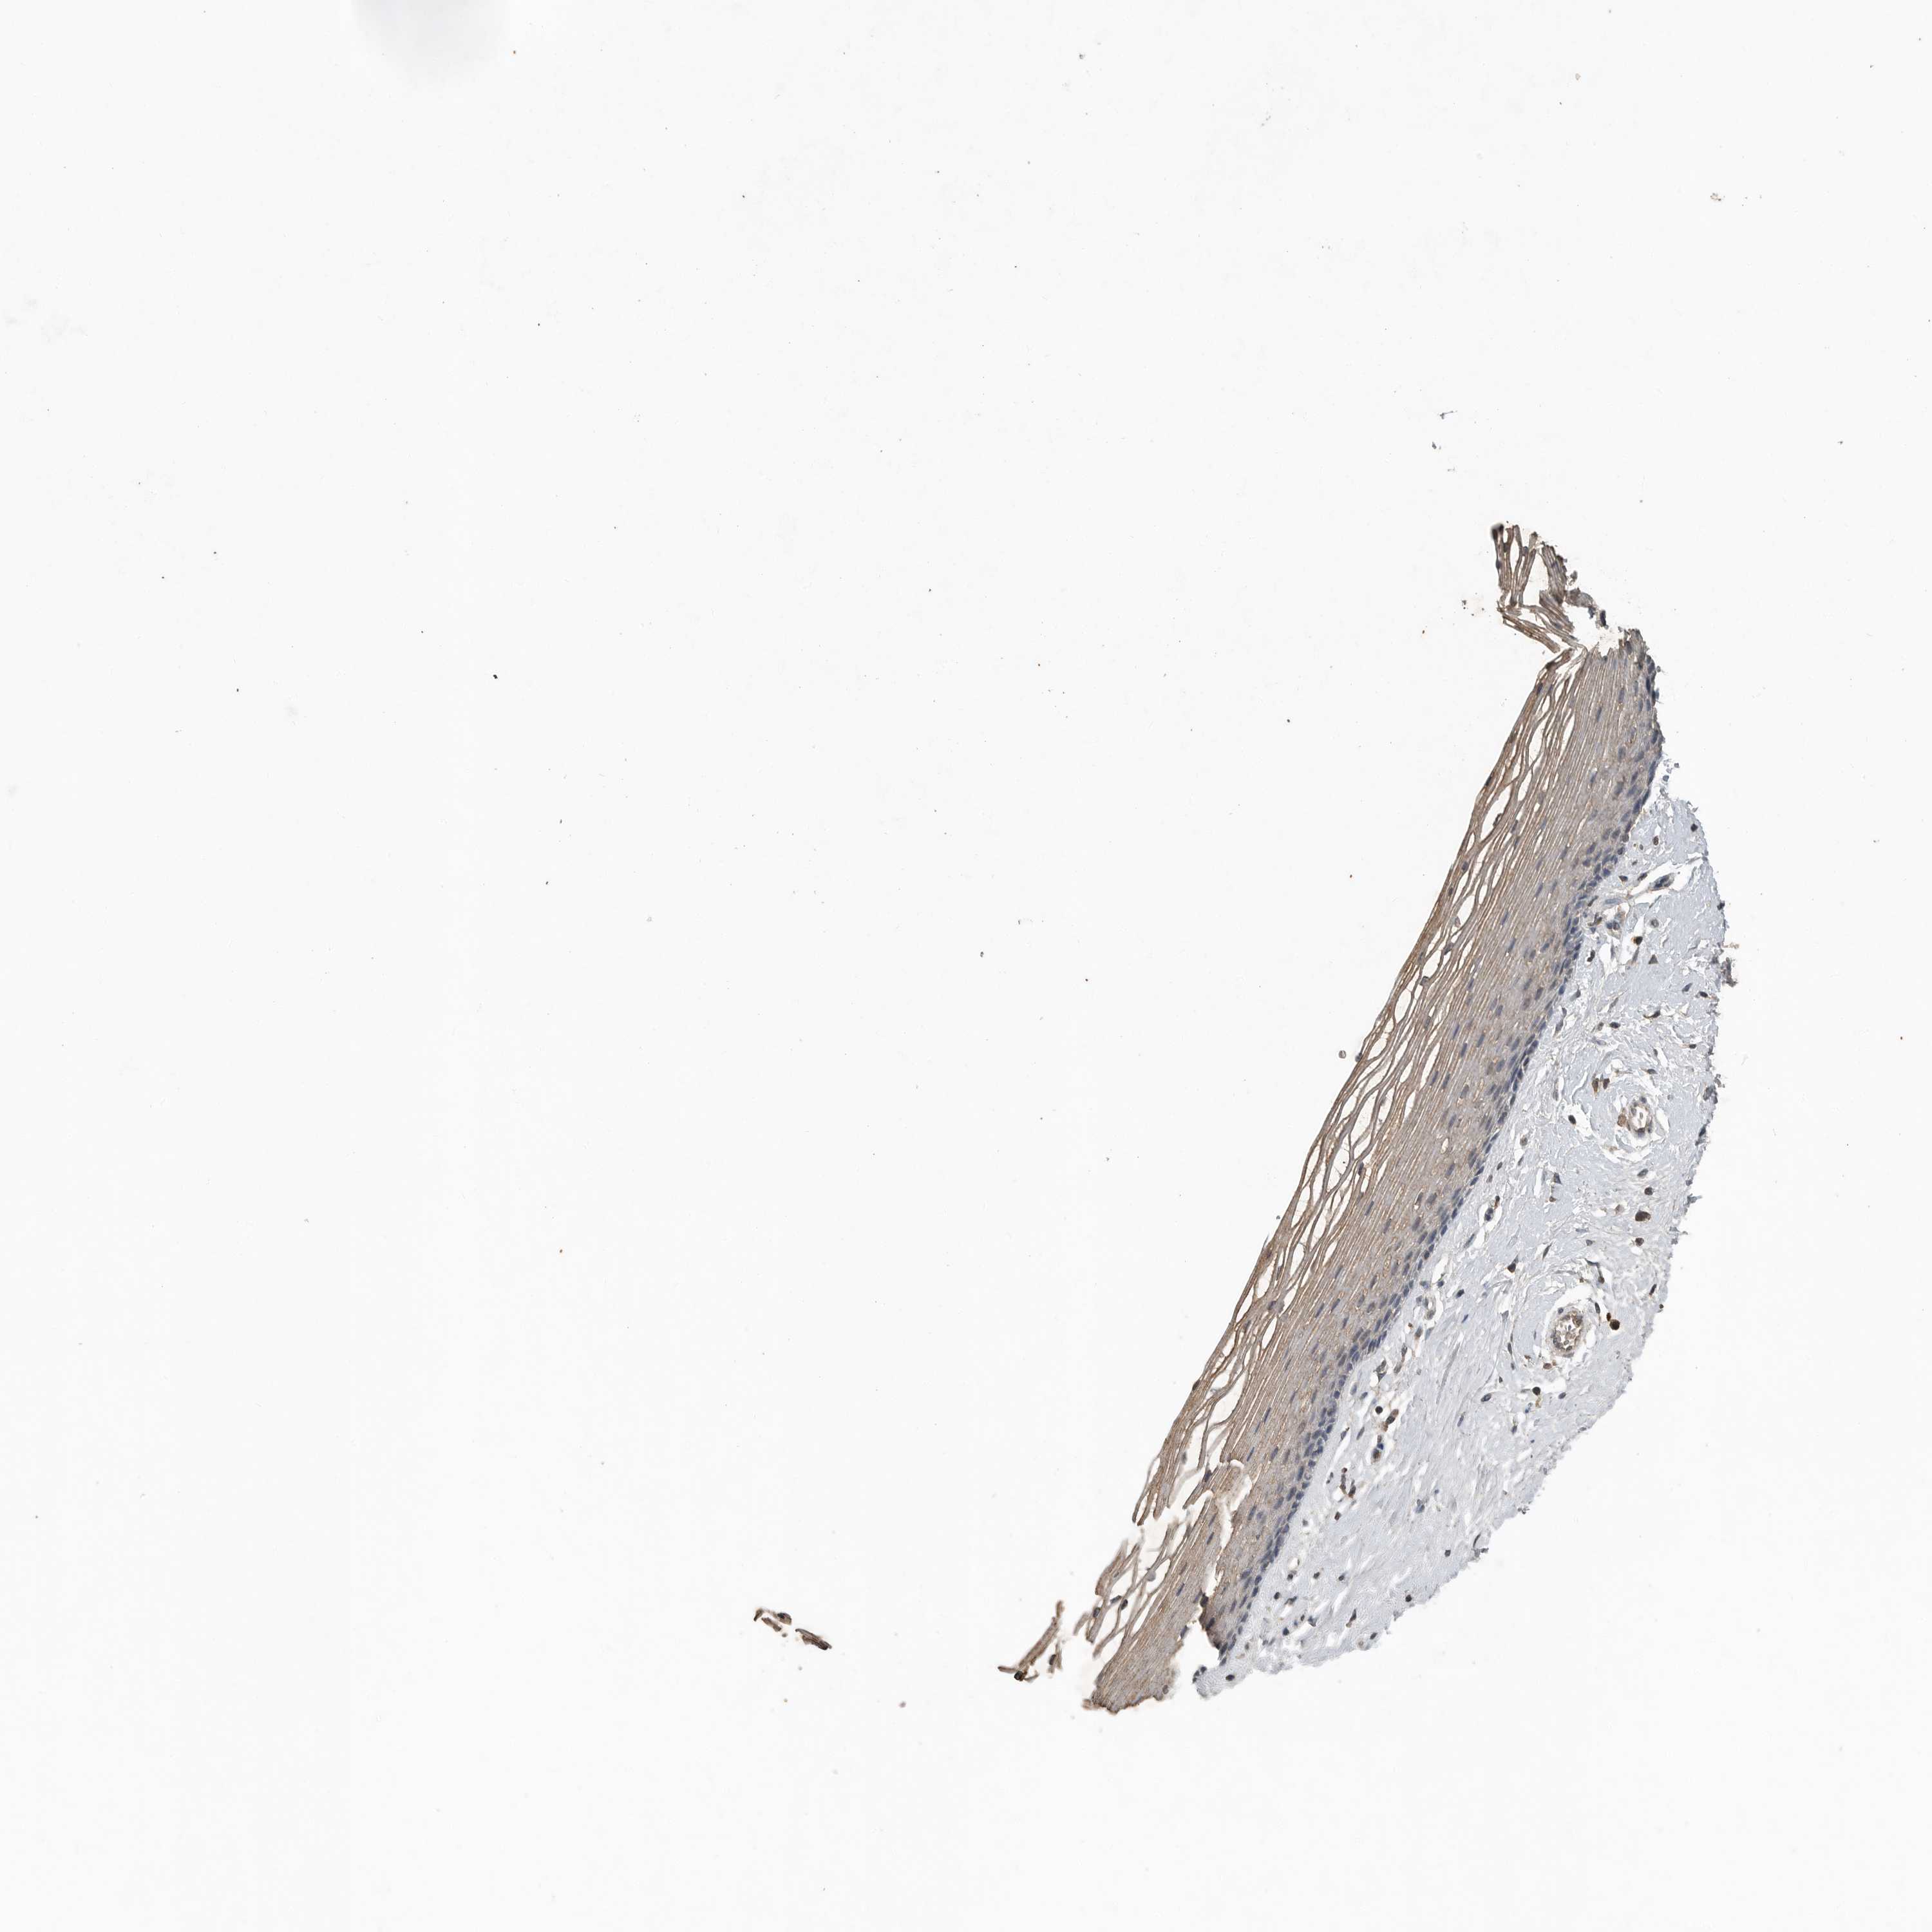

VAGINA - Antibody stainingi

Antibody staining in the annotated cell types in the current human tissue is reported as not detected, low, medium, or high, based on conventional immunohistochemistry profiling in selected tissues. This score is based on the combination of the staining intensity and fraction of stained cells.

Each image is clickable and will lead to virtual microscopy that enables deeper exploration of all samples and also displays staining intensity scores, fraction scores and subcellular localization as well as patient and tissue information for each sample.

Antibody HPA010558Antibody CAB025784

Squamous epithelial cells Not detectedLow